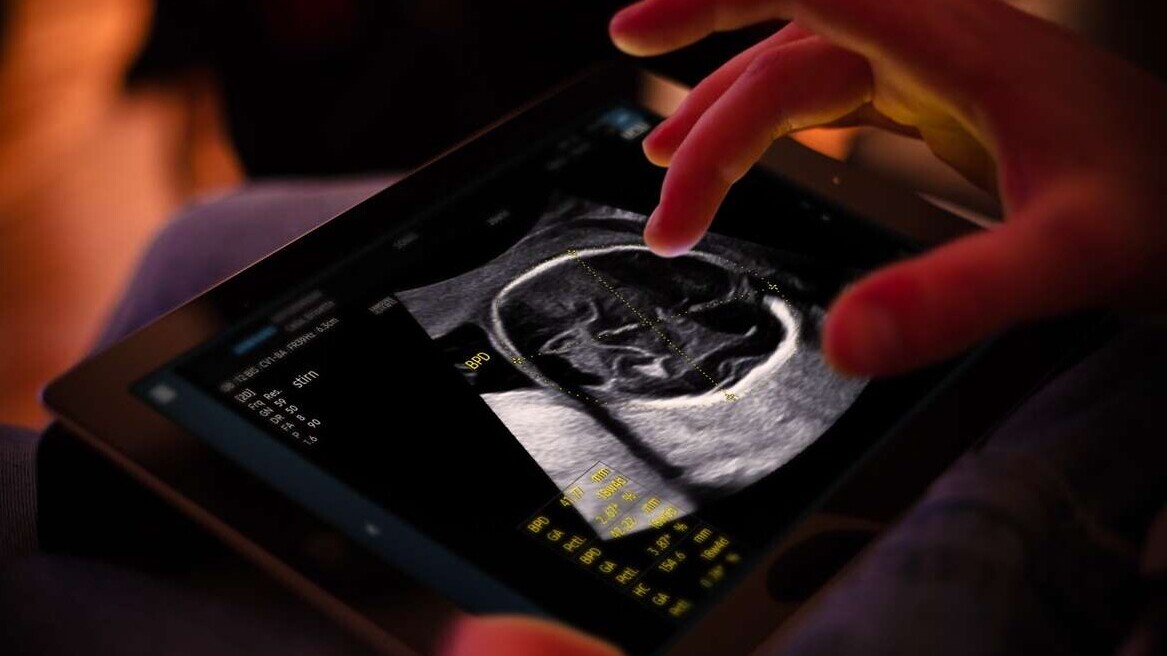

Founded in 2020, Sonio has developed an AI assistant that helps doctors conduct ultrasound exams faster and more accurately. The French startup recently received FDA approval for Sonio Detect, a product that uses deep learning algorithms to improve the image quality of ultrasound scans in real time.

Sonio Detect’s AI model is trained on over a million real ultrasound images. The software is designed to identify prenatal syndromes and abnormalities that doctor’s might’ve missed otherwise.